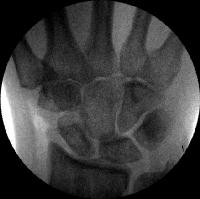

Preop

Click for larger image